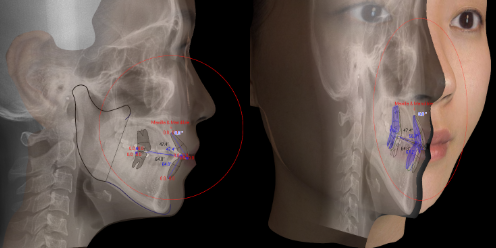

구강 전반 및 얼굴뼈 부위까지 광범위한 진단을 통해 육안으로는 파악하기 어려운 부분까지 살펴볼 수 있습니다.

치료 전,

안모를 분석합니다.

교정치료 결과 후의 모습을 확인 할 수 있습니다.

구강 및 안모의 정보를 모르페우스3D 장비를 이용해 입체적으로 파악 가능합니다. 환자의 입장에서 결과값에 대하여 의료진과 소통을 할 수 있다는 점에서 큰 도움이 됩니다.